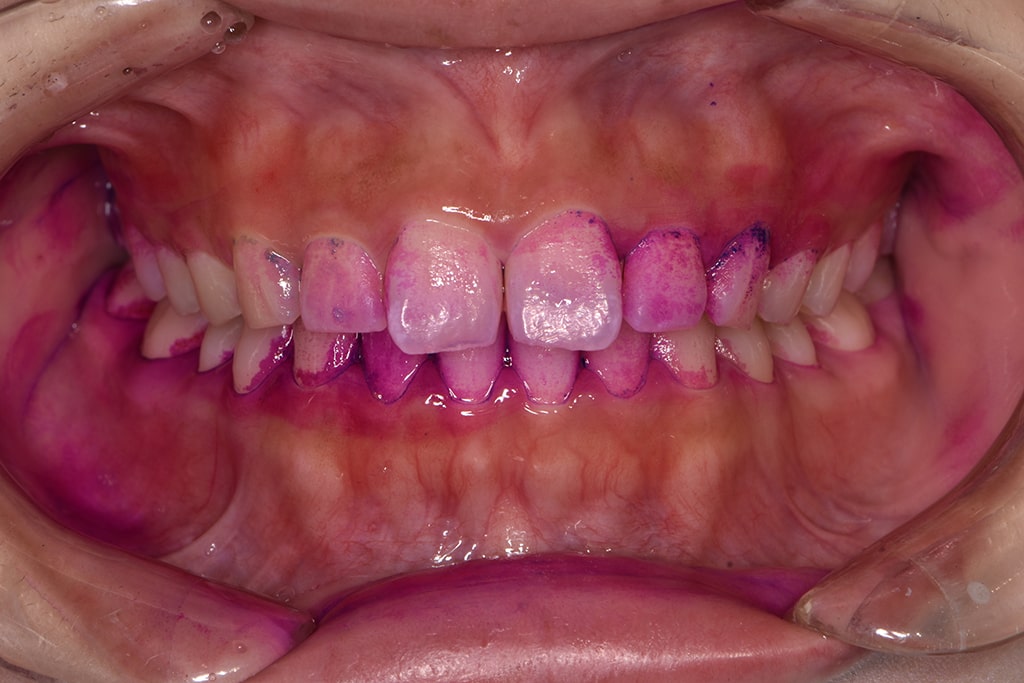

染め出しPCRとブラッシング指導

「染め出しPCR」とは、プラークに色をつけて付着具合を数値化することです。

さらに、染め出したプラークを効率的に除去するために、お一人お一人に適したブラッシング方法をお伝えいたします。

色素とプラーク内の酸の相互作用により、新しいプラークが赤く、古いものが青紫に、そしてう蝕リスクが高い場合は水色に染まります。この染め出しによって、患者様の口内の汚れが視覚的にわかりやすくなり、それが患者様のモチベーション向上に寄与します。

プラークの状態を可視化することで、治療や予防の努力が直接的な成果に結びつき、患者様のオーラルケアへのコミットメントが高まることが期待できます。